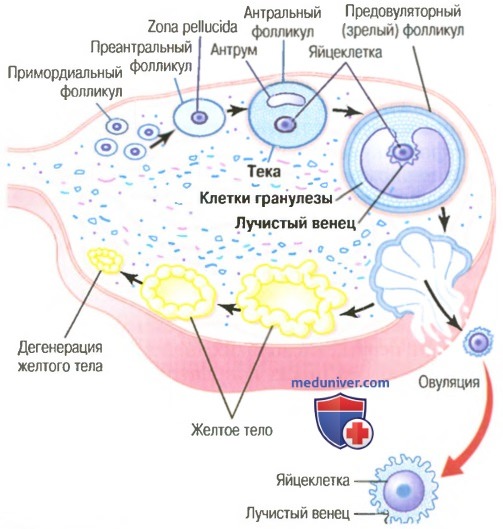

Созревание фолликула в яичнике: этапы и процессы

Раздел: Другие животные